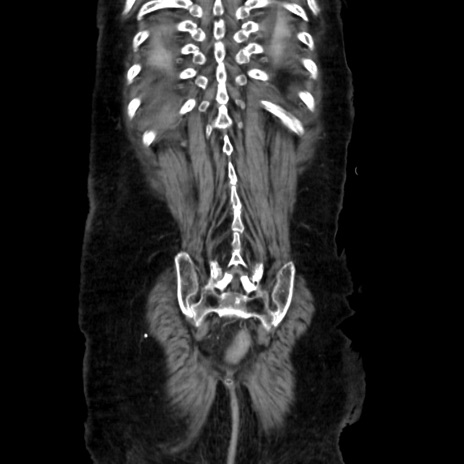

症例40(冠状断像)

【症例】90歳代女性

【主訴】腹痛・嘔吐

【現病歴】 食欲低下、嘔吐があり昨日他院受診。肺炎と診断され入院となる。入院後より腹部全体に圧痛あり。胃管留置され経過みていたが、症状持続するため、

当院転院となる。

【既往歴】胸椎圧迫骨折、胆石症

【身体所見】腹部:中央に激痛あり、圧痛あり、反跳痛不明

【データ】WBC 17100、CRP 18.82

矢状断像